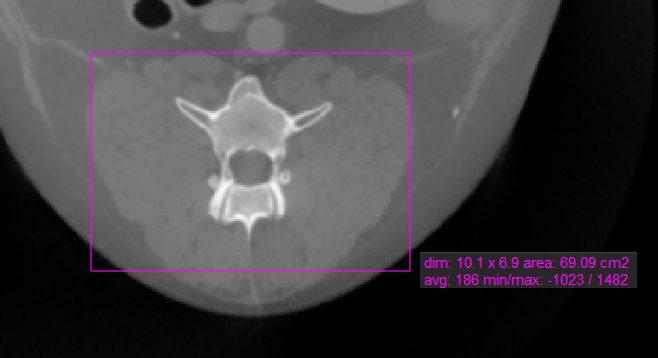

Rechteck¶

Das Werkzeug Rechteck

ermöglicht es dem Benutzer, einen rechteckigen Bereich auf der aktiven Bildschicht zu markieren.

Wählen Sie das Werkzeug Rechteck

aus und weisen Sie es einer der verfügbaren Maustasten zu. Starten Sie die Messung, indem Sie auf die aktive Bildschicht klicken und die Maus ziehen, um eine rechteckige Form zu erstellen. Lassen Sie die Maus los, wenn die Größe des markierten Bereichs zufriedenstellend ist.

Alle verfügbaren Messwerte werden zusammen mit der Messung angezeigt.

Ändern Sie den markierten Bereich, indem Sie einen der vier Punkte der rechteckigen Form mit dem Werkzeug Standard

verschieben.

Einige Messwerkzeuge im CT-Viewer werden verwendet, um einen Bereich auf der aktiven Bildschicht zu markieren. Es gibt vier Werte, die automatisch berechnet und zusammen mit diesen Messungen angezeigt werden.

Dim: Abmessungen der Messung (Breite, Höhe, Abstand)

Fläche: Die mit der Messung eingeschlossene Fläche, berechnet in Quadratzentimetern

Mittelwert: Der durchschnittliche Gewebedichtewert (HU), der durch die Messung erfasst wird. Höhere HU-Werte weisen auf dichteres Gewebe hin, wie z. B. Knochen.

Minimum/Maximum: Der Minimal- und Maximalwert geben den kleinsten und größten Gewebedichtewert an, der durch die Messung erfasst wird.